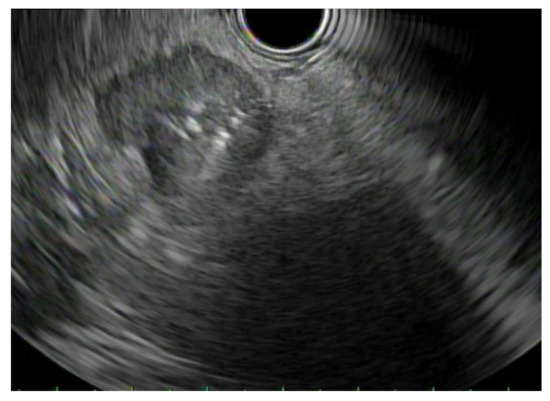

2. Patient Selection and Diagnostic Approach

3. Diagnostic Tests

3.1. EUS vs. Percutaneous Biopsy